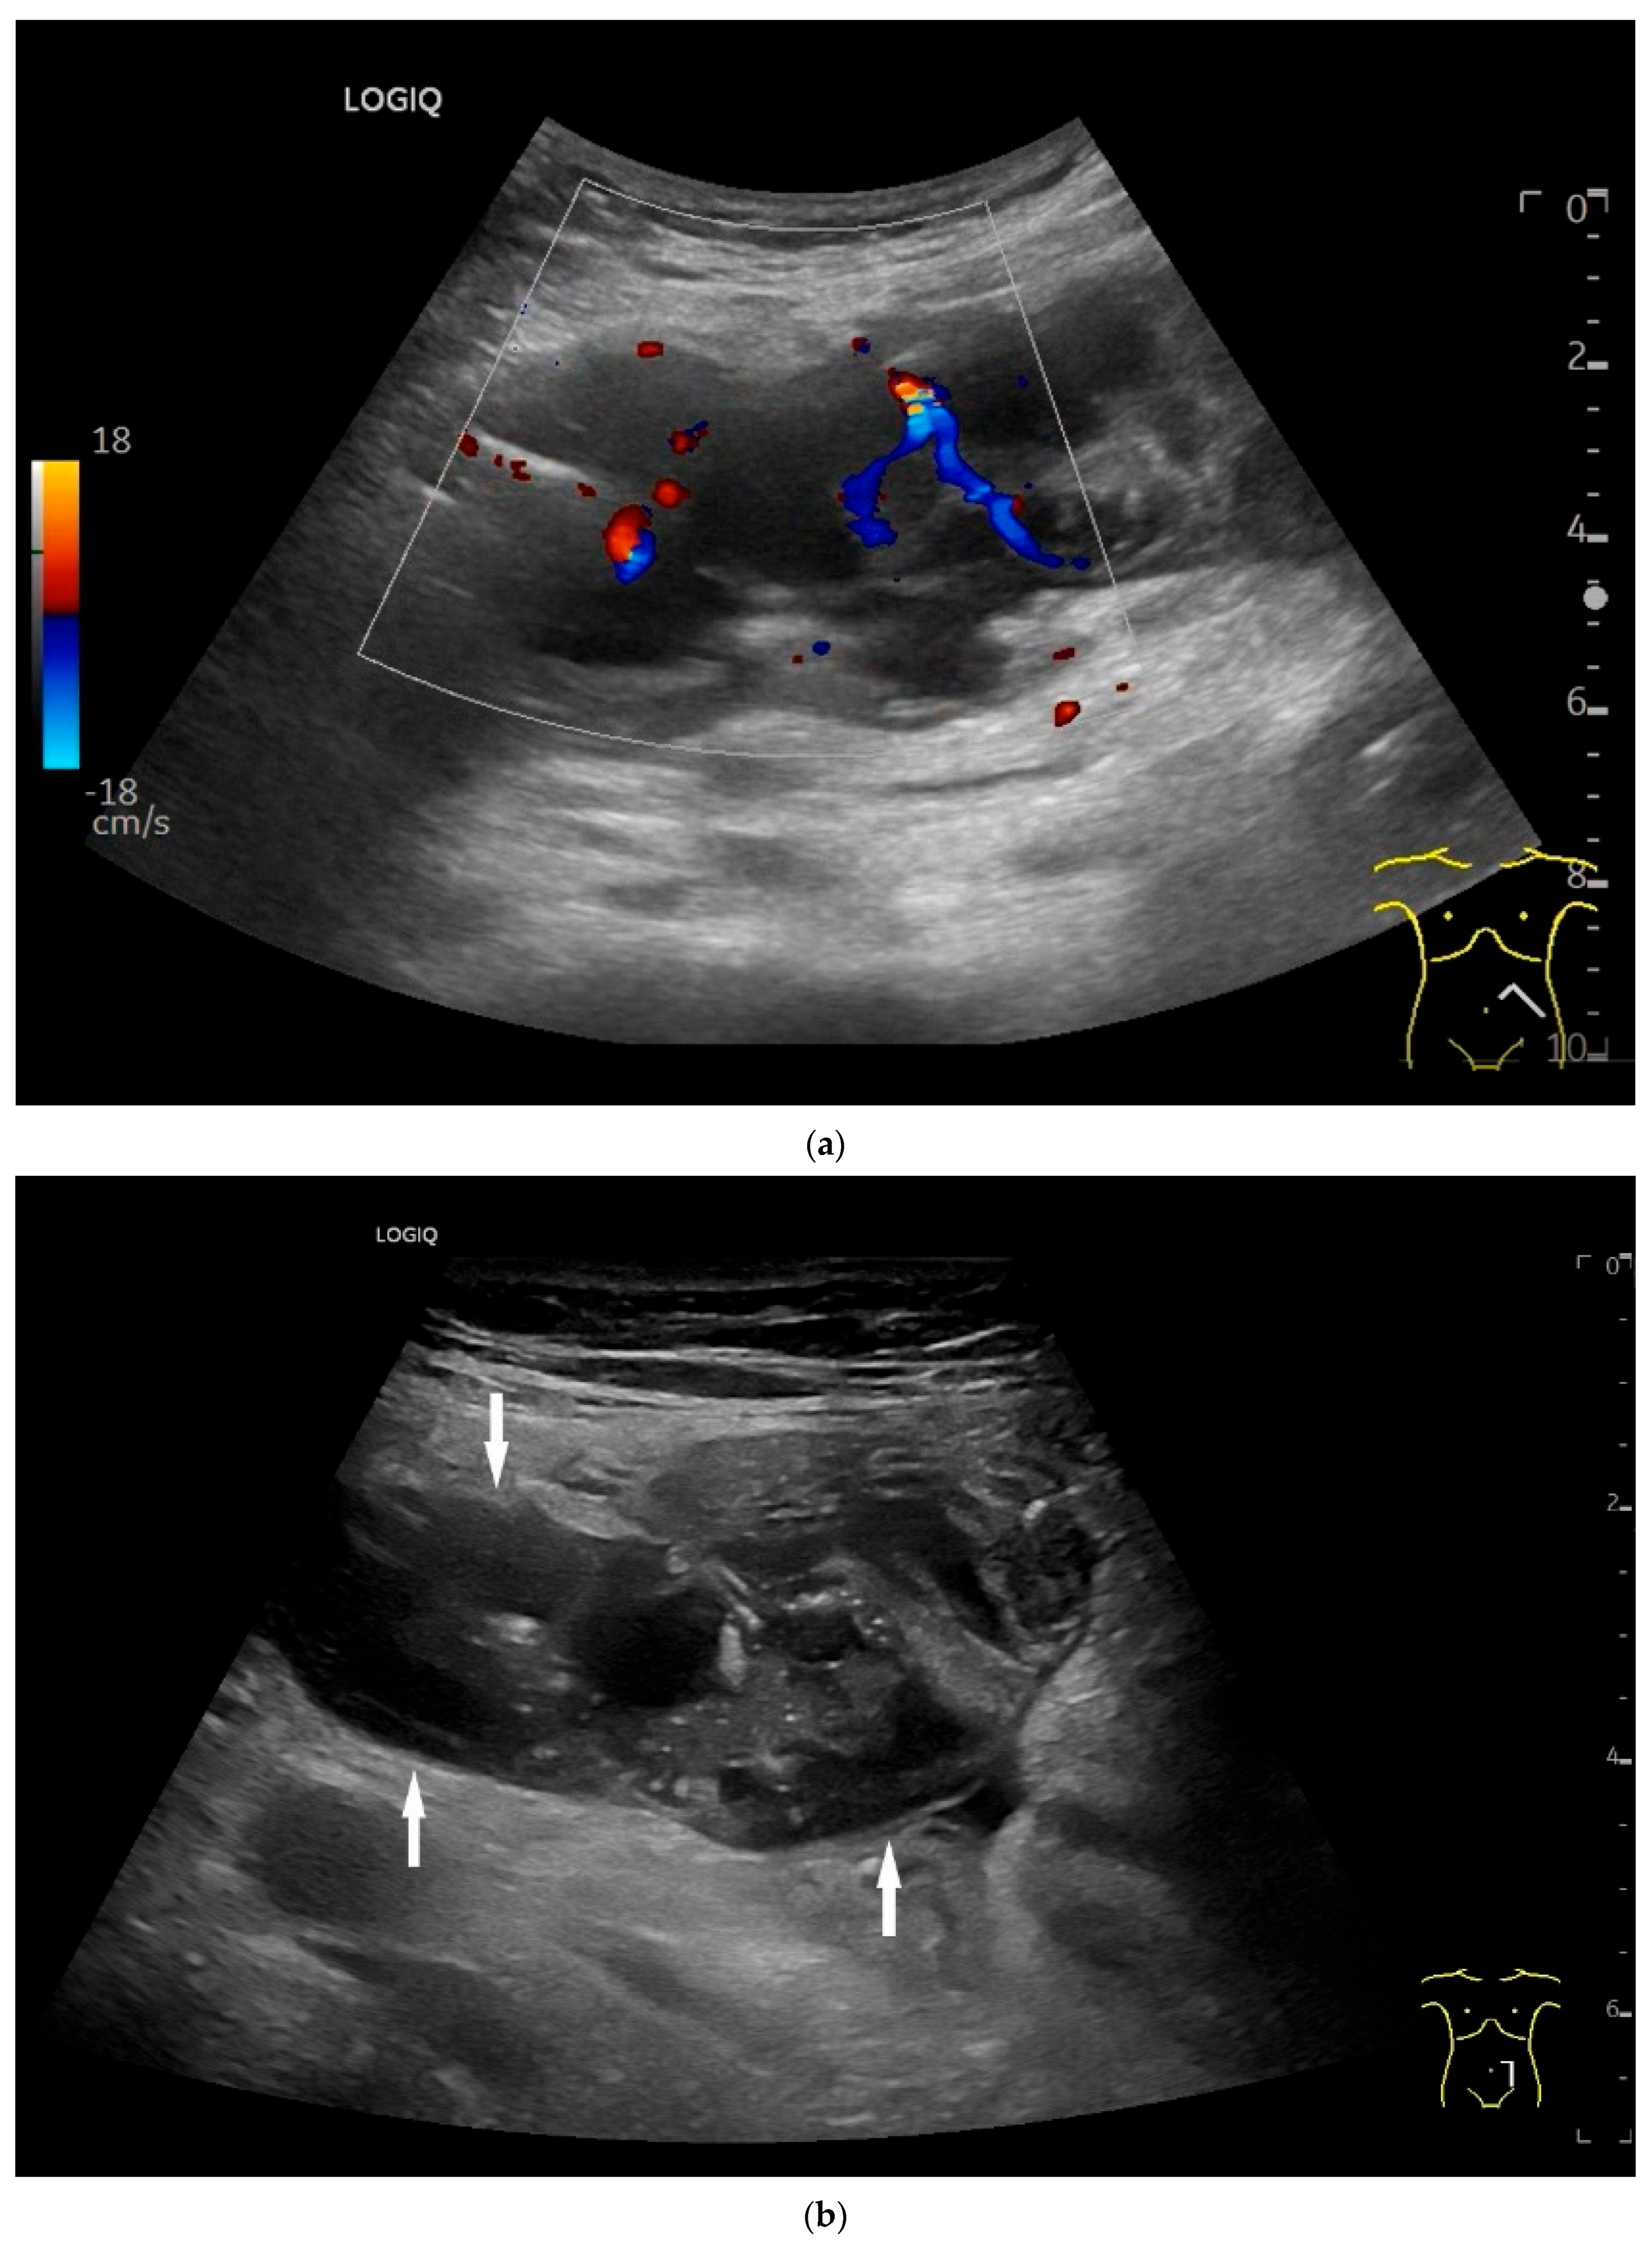

Ultrasound Imaging of Small Intestine NEN

| Neuroendocrine tumor | Small, nodular hypoechoic wall thickenings, mostly in the submucosa with spreading into the other layers. Usually with small vessels on CDI. Regionally enlarged lymph nodes. Multilocular manifestations are possible. |

| Lymphoma | Very pronounced wall thickening with marked hypoechogenicity. Large regional and distant lymph nodes. Look for splenic infiltration. Tumor vessels on CDI and hyperenhancement on CEUS. Heterogeneous hyperechogenicity of the mesentery with walling of the mesenteric vessels. Multiple localizations are possible. |

| GIST | Round hypoechoic masses, homogeneous or heterogeneous depending on size. They usually originate from the muscularis propria, which can be difficult to distinguish in US. Small vessels on CDI, hyperenhancement on CEUS. They move with the small intestine and can change position. |